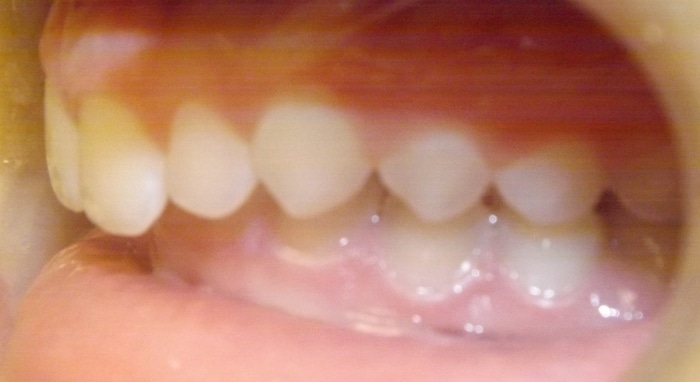

When Marlea presented to us she had a Class II bite with 100% overbite and a 5mm overjet. She also had upper spacing and lower crowding. Marlea’s treatment included metal braces with headgear. With her determination we were able to achieve a Class I bite as well as a perfect overbite and overjet! This is the perfect example of exemplary headgear wear and what a difference it makes in the final outcome of treatment.